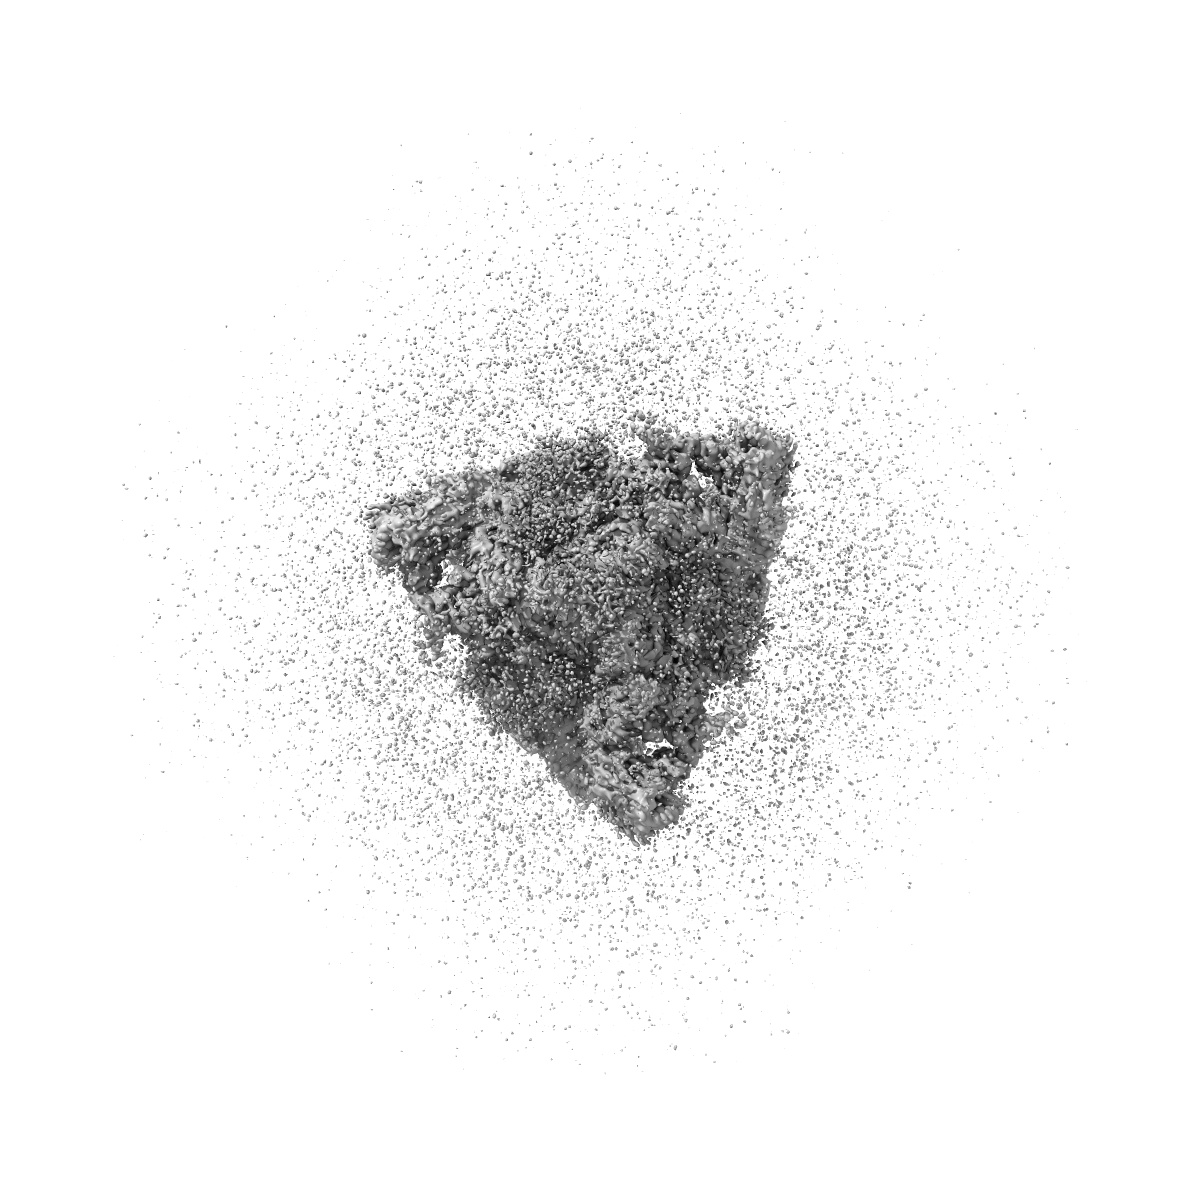

Cryo-EM structure of T/F100 SOSIP.664 HIV-1 Env trimer with LMHS mutations in complex with 8ANC195 and 10-1074

Single-particle3.16 Å

Sample: Cryo-EM structure of T/F100 SOSIP.664 HIV-1 Env trimer with LMHS mutations in complex with 8ANC195 and 10-1074